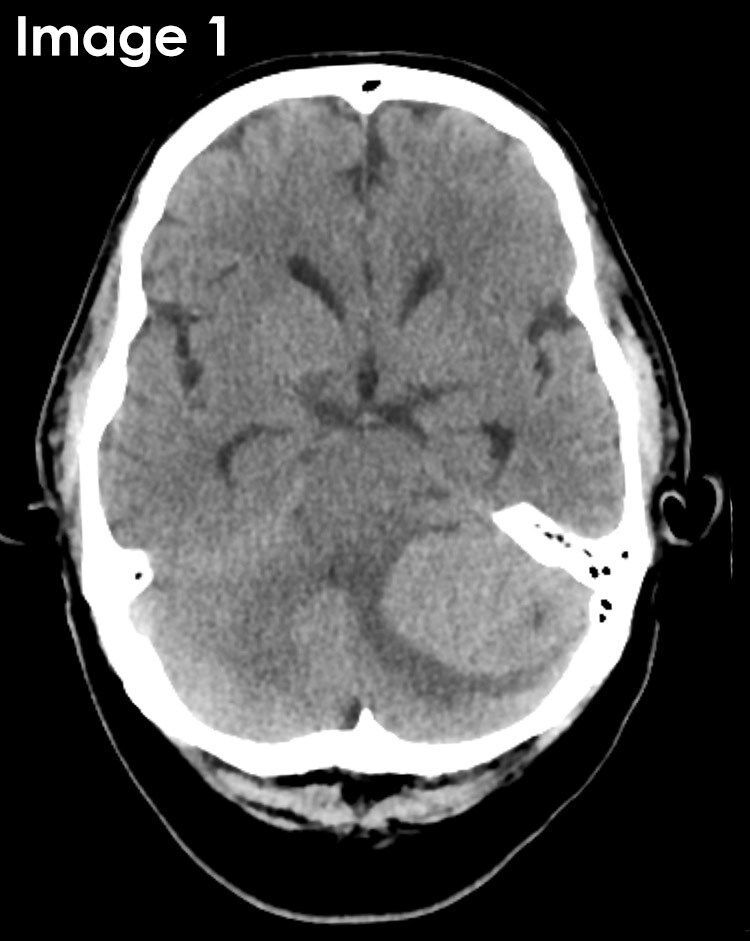

X-RAY QUIZ: Which finding is present on this image?

B: Sail sign

C: Meniscus sign